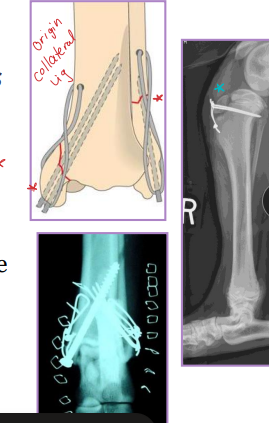

Tension Band Wiring

primary distractive forces

Why: Converts distractive into compressive forces

Patellar, Traction physeal, Olecranon fractures, Tibial crest avulsion

What: Kirschner wires + figure-of-eight cerclage wire (18-22g)

Tibia & fibula Fractures

Considerations: Common, Min soft tissue envelope, risk of open fracture

fibula broke concurrently, not broke in young

Tx:

Rx: Casting/splinting

closed, transverse fractures, >50% reduction, lateral splint (greenstick fractures)

Sx: Plate + screws, IM pin + cerclage, Interlocking nail, ESF

Avulsion: tension band + K-wire, or K-wires alone

Physeal: urgent fixation, cross pins

younger animals